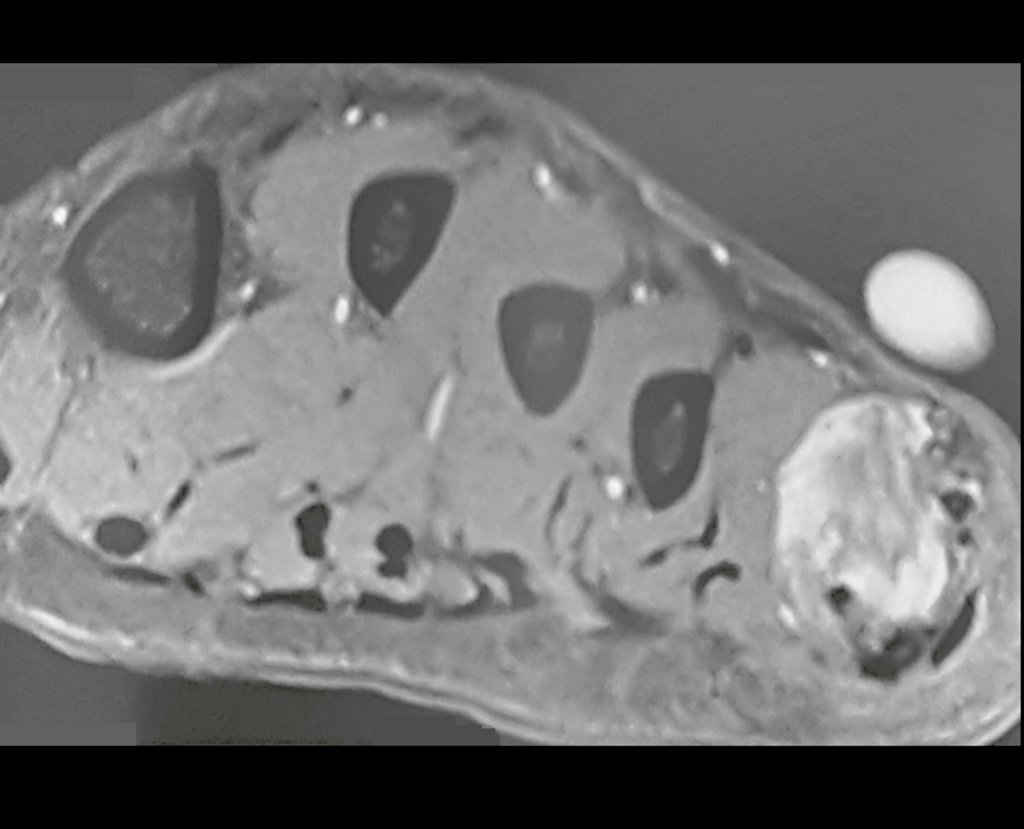

Fibroma desmoide del pie. Paciente de 43 años con “callo” en el quinto metatarsiano del pie izquierdo desde hace veinte años, que desarrolló deformidad, aumento de volumen y dolor en el último año.